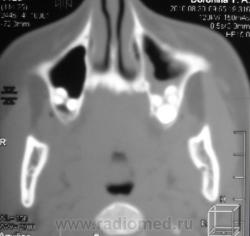

ППН.   Клиника гайморита.

Да, эксудативный левосторонний гайморит, в данной случае следует исключать одонтогенную природу, что более вероятно, вообще на данный момент на всех программных обеспечениях МСКТ, имеется мультипланарная программа с мощью которой все 2 ряда зубов как на ладони, с её помощью  удубнее оценивать состояние альвеолярных бухт, другое дело включена ли она в пакет приобреоенных программ.

Все-таки, гаймароэтмоидит: имеется содержимое в левых клетках решетчатого лабиринта. А почему одонтогенный? Зубы внедрены в пазухи с обеих сторон, оценить состояние периапикальных мягких тканей слева из-за жидкости не предсталяется возможным.